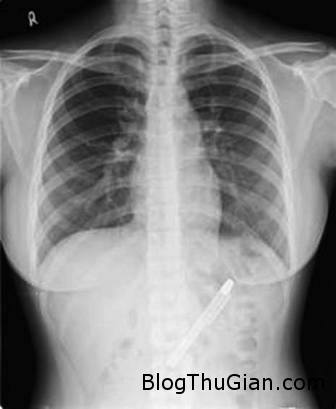

Ảnh chụp X-quang cho thấy chiếc bút trong bụng bệnh nhân.

Chiếc bút được phát hiện sau khi bệnh nhân được nội soi và chụp X-Quang.

Các bác sĩ cho biết chiếc bút này đã nằm trong cơ thể bệnh nhân suốt một thời gian dài và đã bị hoen gỉ do môi trường axit trong dạ dày. Nếu chiếc bút không được phát hiện và loại bỏ sớm thì nó có thể gây ra những biến chứng nguy hiểm hơn, thậm chí ảnh hưởng đến tính mạng.